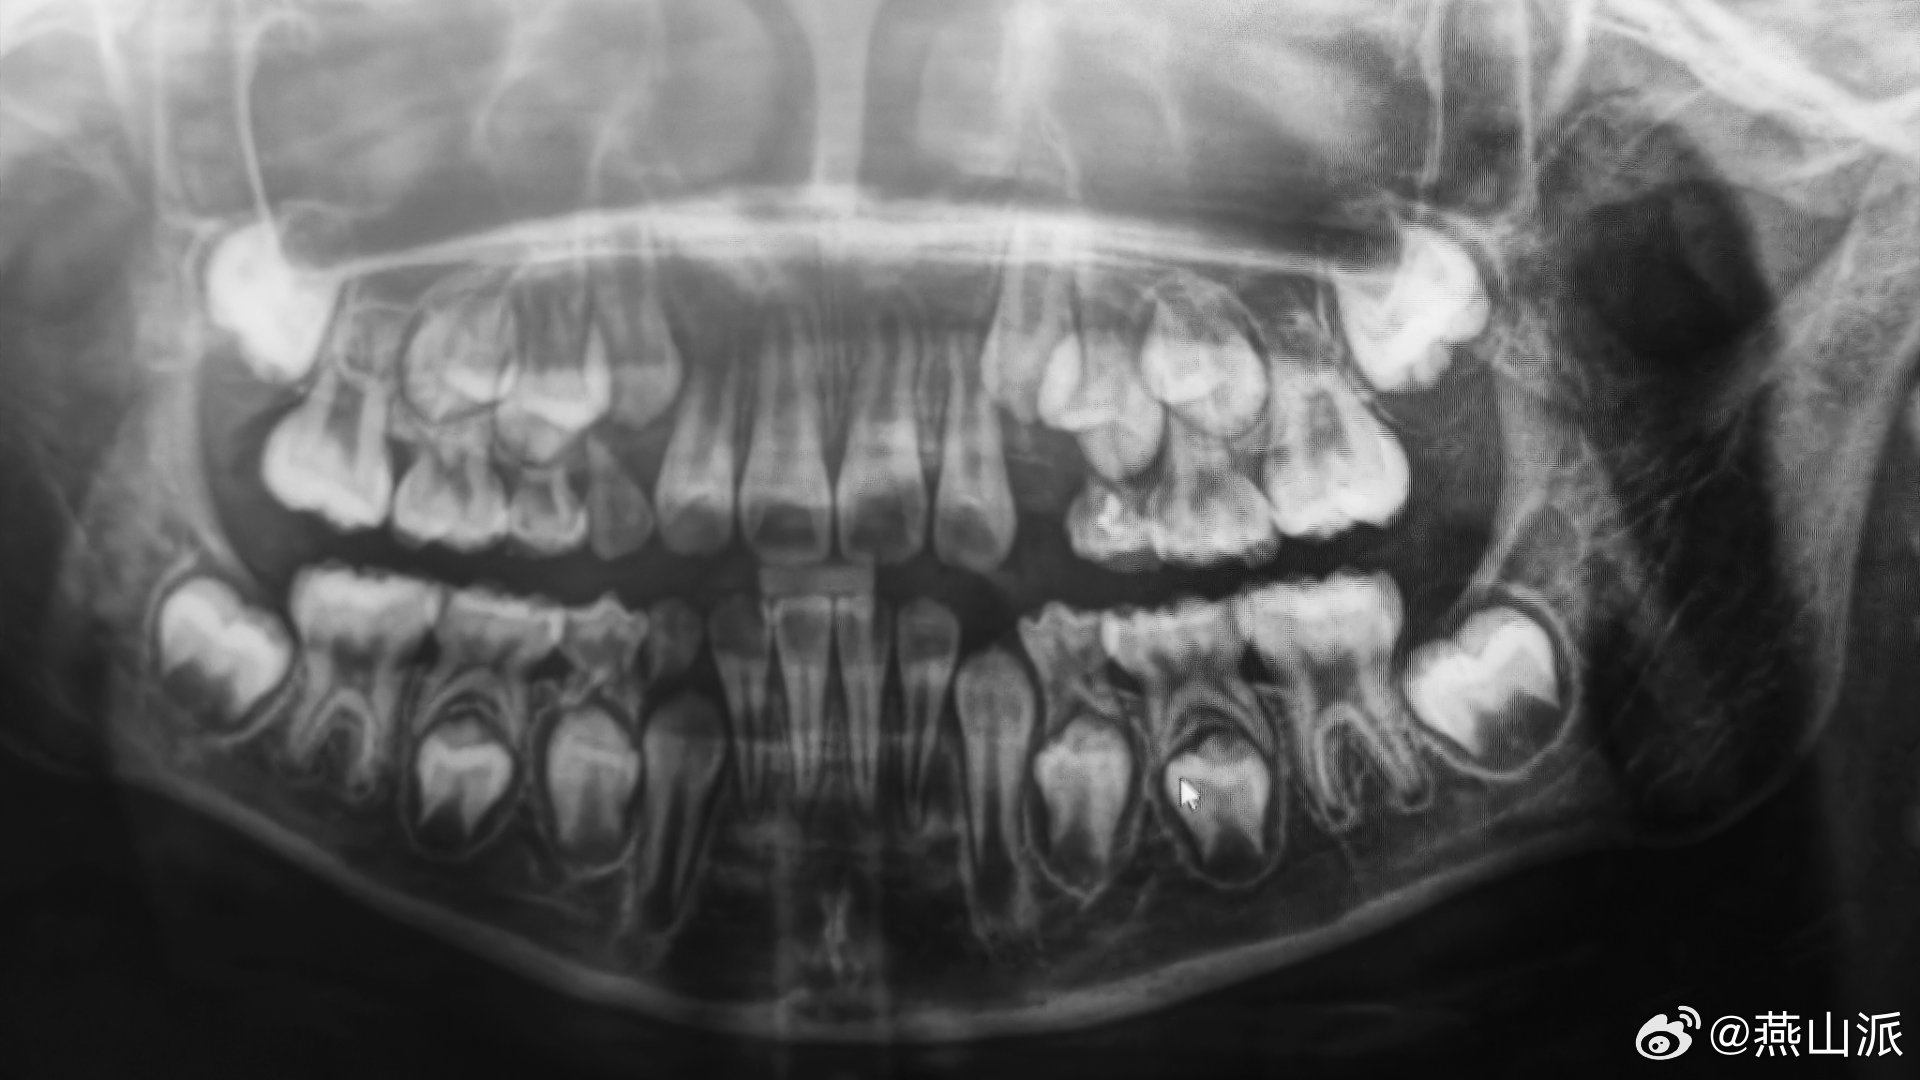

“乳牙是被恒牙顶掉的”这一刻是不是具象化了?